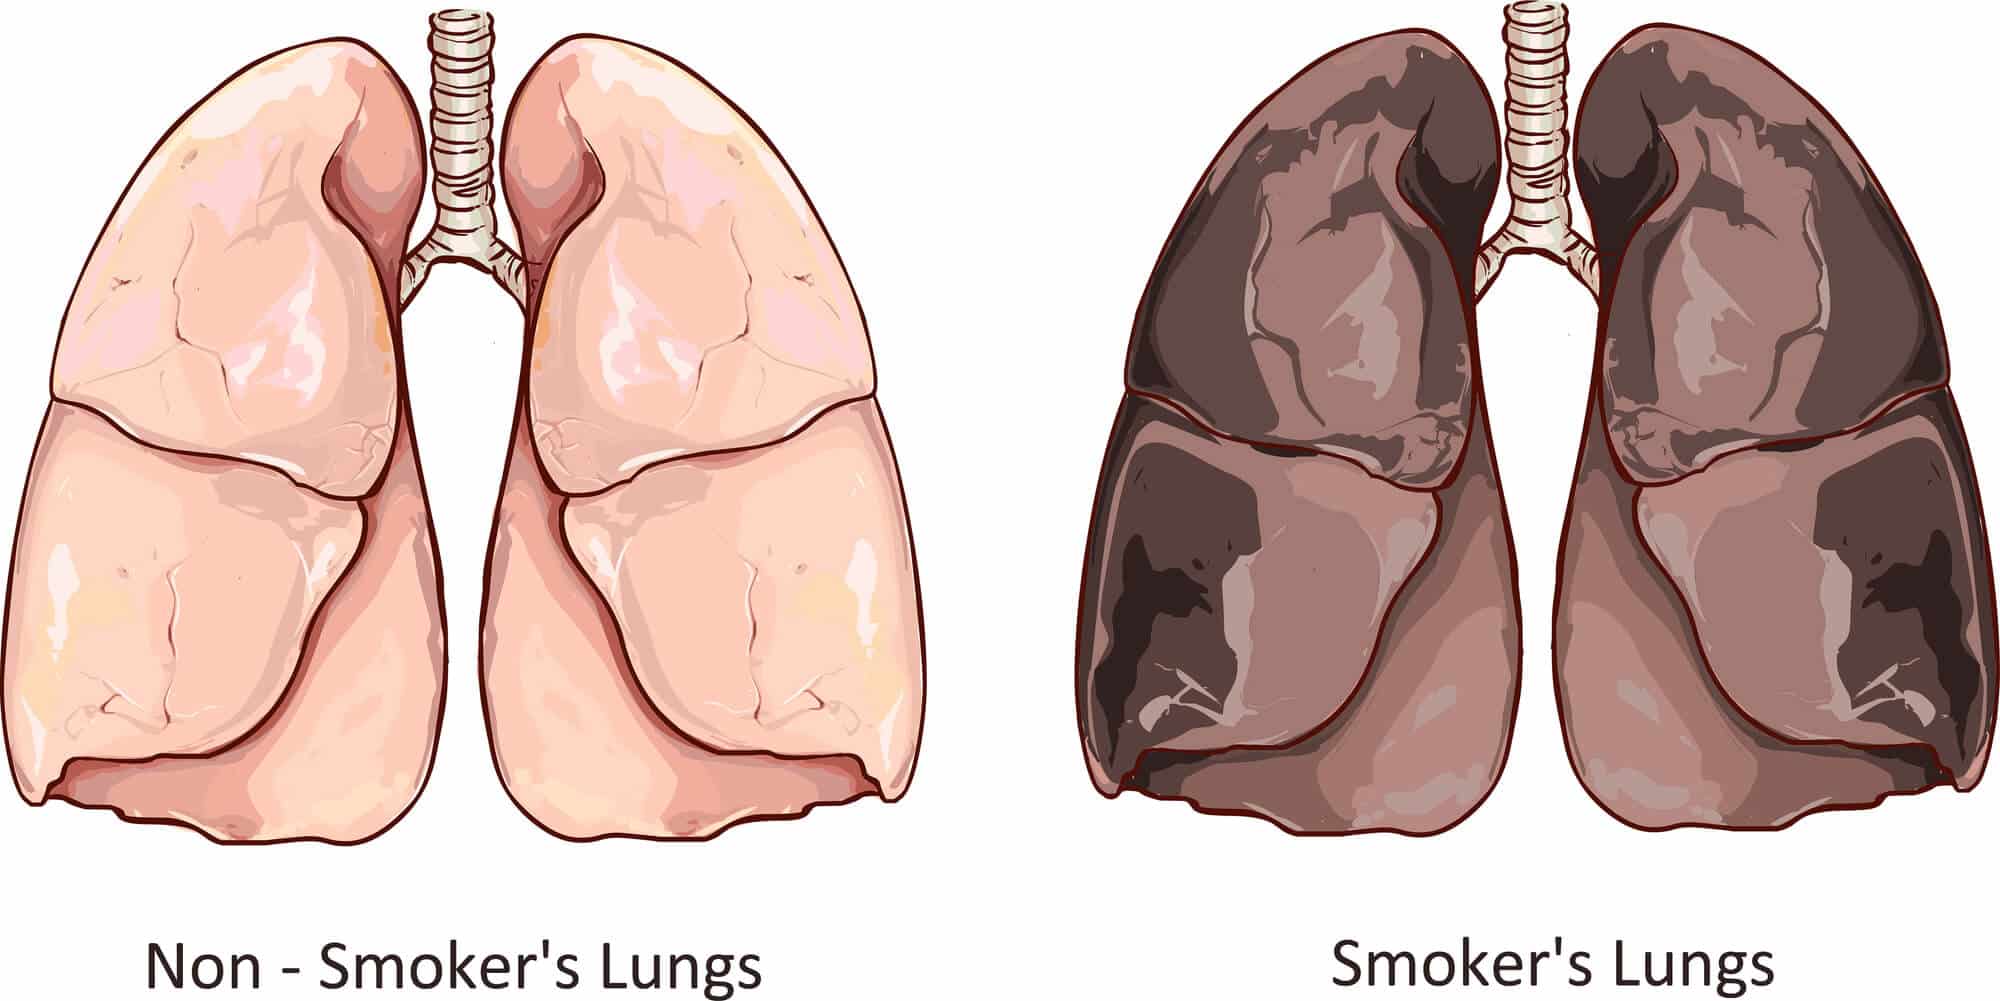

Здоровые Легкие Картинки

Здоровые Легкие Картинки 117 фото